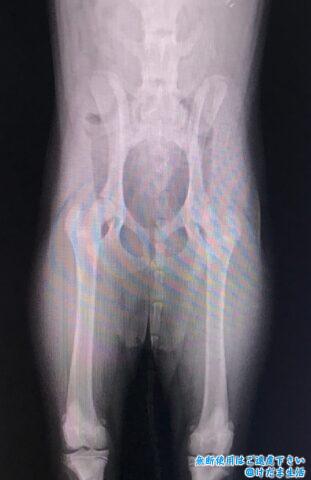

生後6ヶ月のレントゲンの時点では、成長線がまだはっきり残っていました。

獣医さんはつるちゃんの抵抗や違和感のあるポイントを探し出してくれて、左前足の薬指と手首、右前足の人差し指、左ヒザに抵抗を示すのでポイントを絞ってレントゲン検査。

レントゲンの結果も関節液の増加などの炎症は見られず、前足は正常。

しかし1歳過ぎの時点で両膝の成長板が閉じてないことが判明。